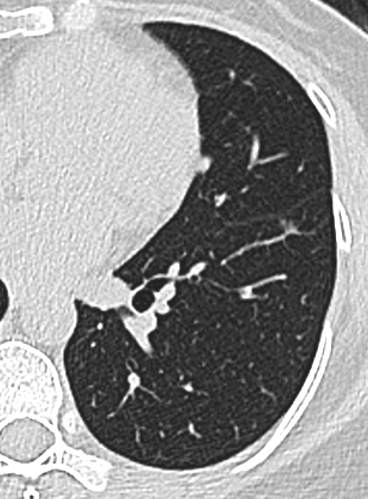

中年女性,既往体健。

21年底左下肺,直径5.2mm:

23年初复查CT左下肺GGO有所增大,直径:6.9mm